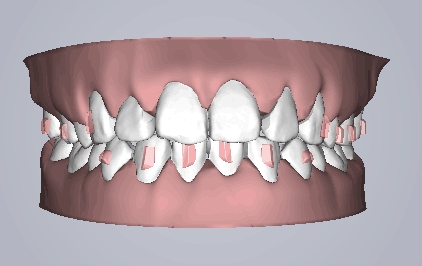

治疗方案动画

治疗预计效果和实际效果